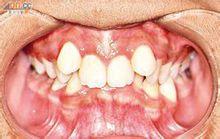

正鎖頜是上後牙舌尖的舌斜面在下後牙頰尖頰斜面的頰側,頜面無咬合接觸。個別後牙正鎖頜及單側多數後牙的正鎖頜在臨床較為多見。

反鎖頜是上後牙頰尖的頰斜面在下後牙舌尖舌斜面的舌側,頜面無咬合接觸。該錯頜在臨床上較少見。